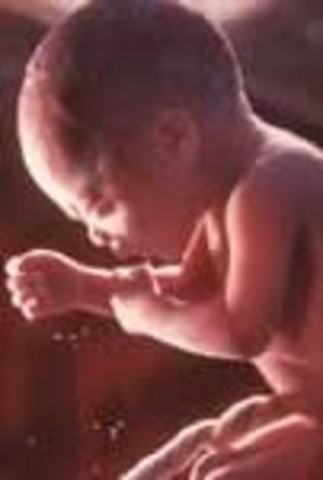

• Week 27: Eyes Can Open

Week 27: Eyes Can Open

This is the start of the third trimester and the baby now looks almost exactly how it will when it is born. The eyes can now fully blink.

• Week 28: May Recognize your Voice

Week 28: May Recognize your Voice

The fetus' milk teeth have fully developed under its gums. Talking, reading, and singing to the baby will sooth it and slow its hard rate down.